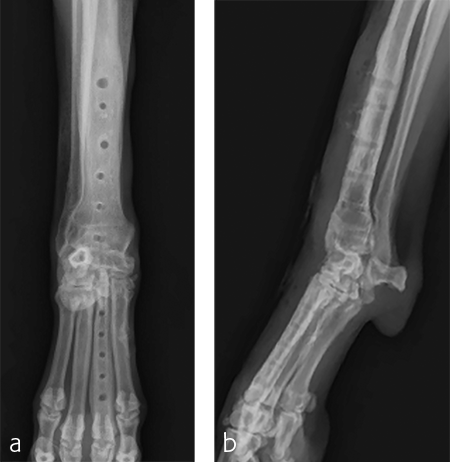

A 7-year-old, 32.5 kg, Labrador Retriever became acutely lame on the left thoracic limb while catching a ball. It was evaluated three weeks later and had carpal swelling, pain, and instability of the left carpus. Flexed lateral, craniocaudal, and extended mediolateral view images of the left carpus revealed a dorsal chip fracture at the carpometacarpal joint and hyperextension of the left carpus (Fig 9).

Treatment with a splint for several weeks resulted in no improvement. A pancarpal arthrodesis was performed with the 2.7/3.5 Pancarpal Arthrodesis Plate and a combination of standard cortical and locking screw fixation. An autogenous cancellous bone graft was collected from the left proximal humerus and placed at all joint levels.

Immediate postoperative images confirmed anatomic alignment and adequate carpal extension (Fig 10). At the 11-week postoperative follow-up examination, functional recovery was very good with images revealing stable implants and healing of the arthrodesis (Fig 11). The dog was then allowed to return to normal activity.